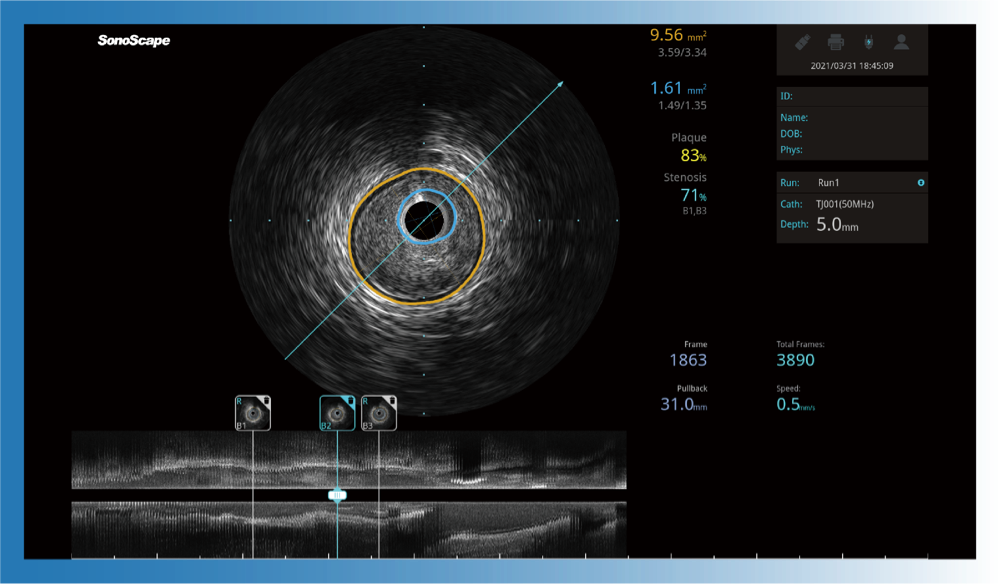

对比传统IVUS导管成像,玖鼎集团宽频IVUS图像的近场支架梁显影更细腻,远场中膜外血管仍清晰可辨,兼顾远中近,兼顾分辨力与穿透深度

一键智能描迹,自动测量斑块负荷、面积狭窄率等指标,准确率高于90%